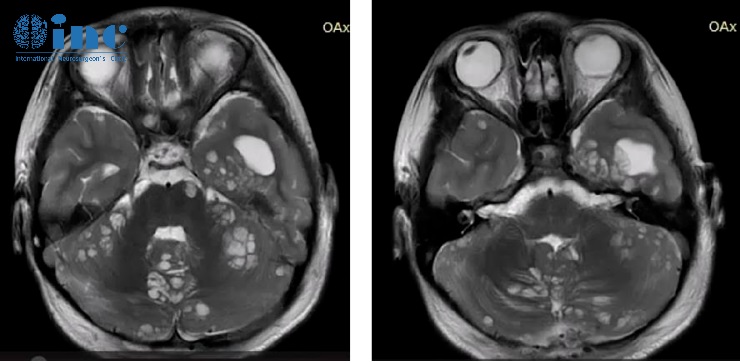

脊柱磁共振显示脑膜弥漫性强化,脑膜覆盖多处结节性病变,以及实质内病变和结节性小囊肿。

颅脑磁共振序列可见脑膜明显强化,是脑干腹侧表面上的软脑膜。

小脑弥漫性可见多发囊性病变,特别是上叶正中区和上蚓部,可能导致脑脊液循环障碍伴继发性脑室扩张。

从文献中提取的一些图像说明了刚才提到的情况:增强的蛛网膜的病理性增粗,肿瘤的多个结节状定位,相关的脑积水。大脑的非强化局灶性囊性病变是由血管周围间隙的局灶性扩大造成的,也是因为脑脊液循环受阻而扩大。